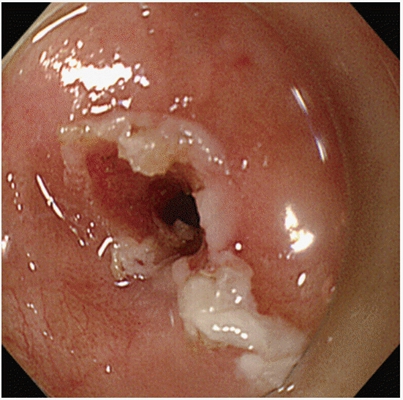

子宮頸癌前病變圖片

宮頸癌的早期症狀

宮頸癌的早期症狀

宮頸癌的早期症狀

宮頸癌的早期症狀

宮頸癌的早期症狀

宮頸癌的早期症狀

宮頸癌的早期症狀

宮頸癌的早期症狀

宮頸癌的早期症狀

宮頸癌的早期症狀